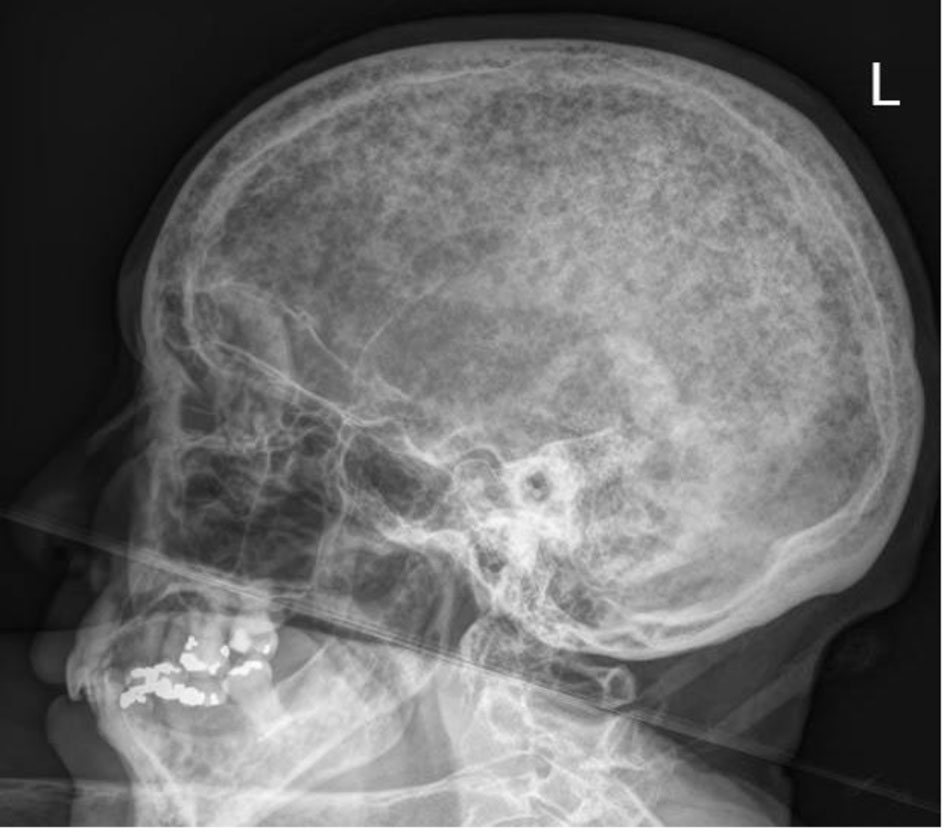

The skeletal survey seen in Figure 1 demonstrated the significant progression of her disease, especially near the skull base. Magnetic resonance imaging (MRI) of her brain, seen in Figure 2, revealed that the patient had myelomatous lesions at the right occipital condyle and clivus consistent with MM disease advancement. The cause of her dysarthria was concluded to be hypoglossal nerve mononeuropathy, due to impingement as the nerve courses through the hypoglossal canal, located at the base of the right occipital condyle. Although the patient did understand that all of her conditions stemmed from poorly controlled disease, she did not desire to pursue further chemotherapy or receive blood transfusions at the time.

![]() Click for large image | Figure 1. Skeletal survey of the skull demonstrating extensive punched out lesions consistent with advanced disease. |